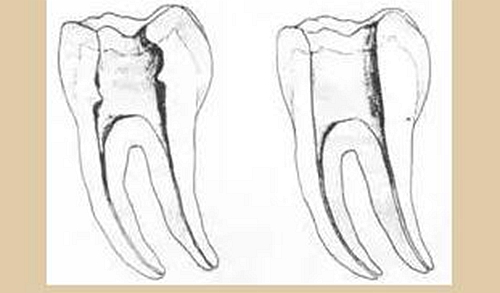

三、開髓孔

1. 正常開髓孔的位置和大小

左圖為正常開髓孔的大小和位置。左邊圖為下顎,右邊圖為上顎。